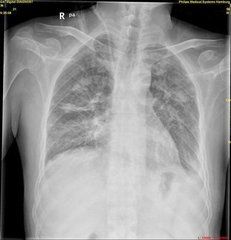

4.X線胸片典型表現為雙下肺廣泛的小片狀或大片狀滲出性陰影,並可在短期內迅速變化。

1.胸部X線

(1)肺部的影像特點:

①形態多樣:可呈蝶翼狀、粟粒狀、孤立或瀰漫小片狀,單發或多發大片狀,團塊狀或多髮結節狀等各種陰影,典型的蝶翼狀少見,占4%~10%左右,肺紋理增多、粗亂最常見,占71%。

②密度不等:密度可淡可濃,可均勻或多種影像混雜。

③位置不定:可居於兩側或一側肺部,可位於兩側全肺或兩肺中下野,亦可見於一側全肺或某一肺葉肺段。總的印象:右肺多於左肺,中內帶多於外帶,中下肺葉多於上肺葉,右肺下葉極易受侵犯。

④變化較快:經血液透析、強心、利尿等治療後,隨著腎、心功能的改善,肺部陰影短時間內可明顯吸收或完全消散。

(2)肺部影像分型

①肺淤血症型:臨床最常見,約占60%,表現為雙肺門陰影增大、模糊,肺紋理增粗。

②間質性肺水腫型:肺門影增大,邊緣不清,上下肺紋理增多、增粗和模糊。約13%出現K線,B線占7%,A線2%~3%。

③肺泡性肺水腫型:兩下肺出現廣泛小片狀或大片狀影,密度不高,連續且模糊,典型者即蝶翼狀。此型占臨床19%左右。

④肺間質纖維化型:肺野內多數條索狀及格線狀陰影,約占臨床21%。

⑤心臟擴大:肺泡性和間質性水腫型多見心臟擴大和心力衰竭,心∶胸>0.5者占61%。

⑥胸膜炎:少量或中等積液,一般只肋膈角變鈍,臨床占31%。